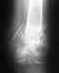

Перспектива эндопротезирования в 38 лет не очень привлекательная.

В любом случае, без свежих рентгенограмм начать обсуждение не получится.